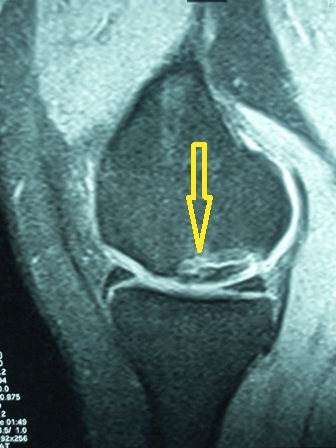

26 yaşında erkek hasta sol diz burkulması sonrasında tekrarlayan boşluğa basma hissi, dizde güvensizlik, ağrı ve şişme şikayetleri ile başvurdu. Artroskopik ön çapraz bağ rekonstrüksiyonu ameliyatı (ACL Reconstruction) ile tedavi edildi.